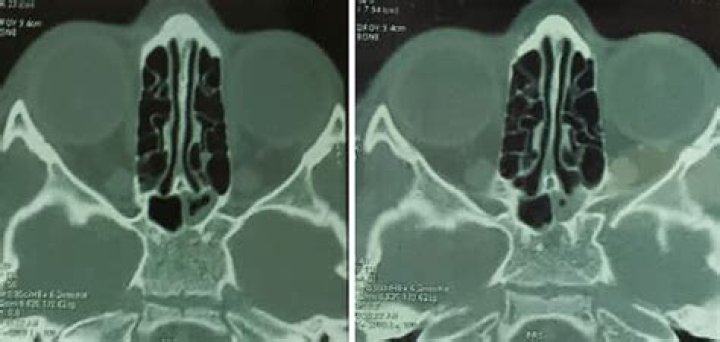

2) while partial opacification was defined as at least one-third of the maxillary sinus being opacified without clear distinct boundaries (Fig. 3). Complete opacification was a completely opacified maxilla in all axial and coronal slices (Fig. 4).